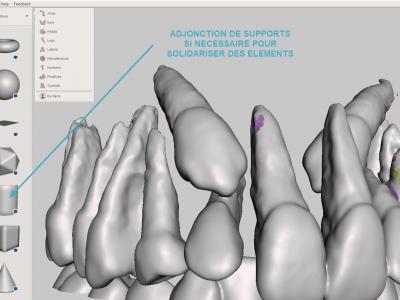

- Etape de solidarisation : si certaines dents ne sont pas en contact avec d'autres, les solidariser avec l'adjonction de cylindres, puis fusionner les éléments avec l'outil "combine"

Avec votre logiciel habituel d'impression 3D. Pensez à orienter votre modèle afin de ne pas être gêné par les supports.